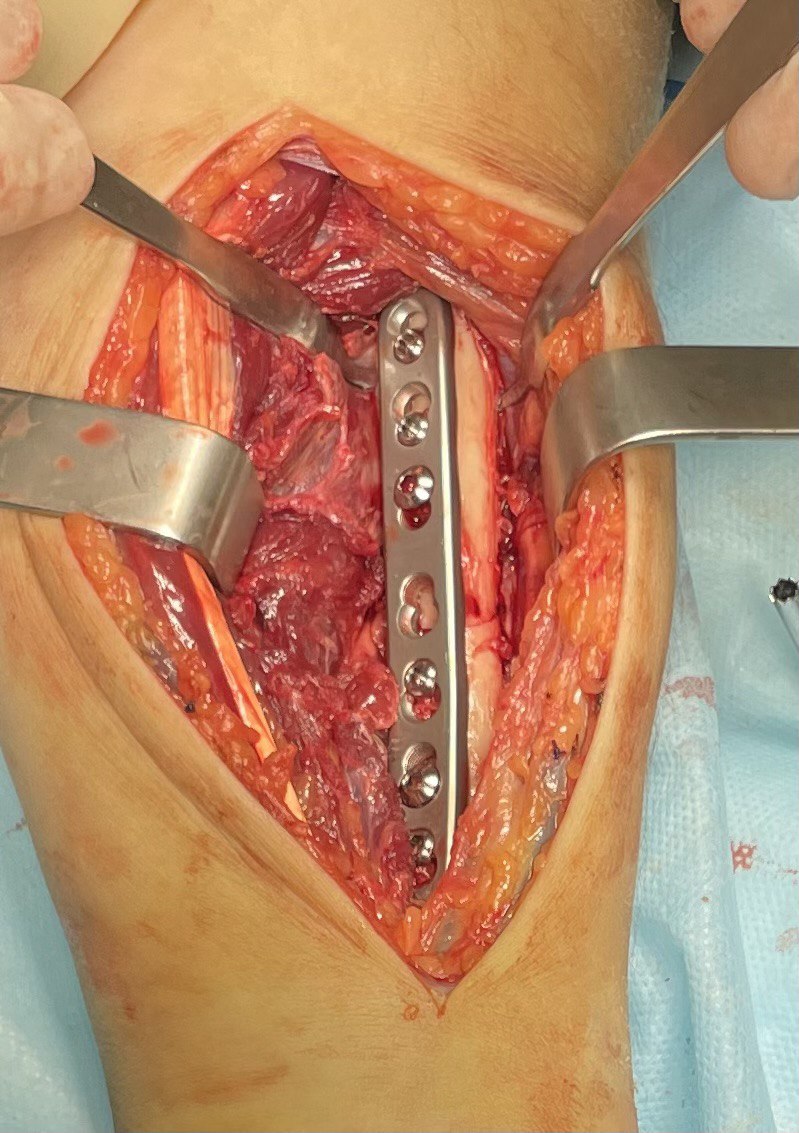

Клинический случай: внутрисуставной перелом дистального метаэпифиза лучевой кости — операция (остеосинтез пластиной)

Этап остеосинтеза: доступ, фиксация и контроль положения пластины.